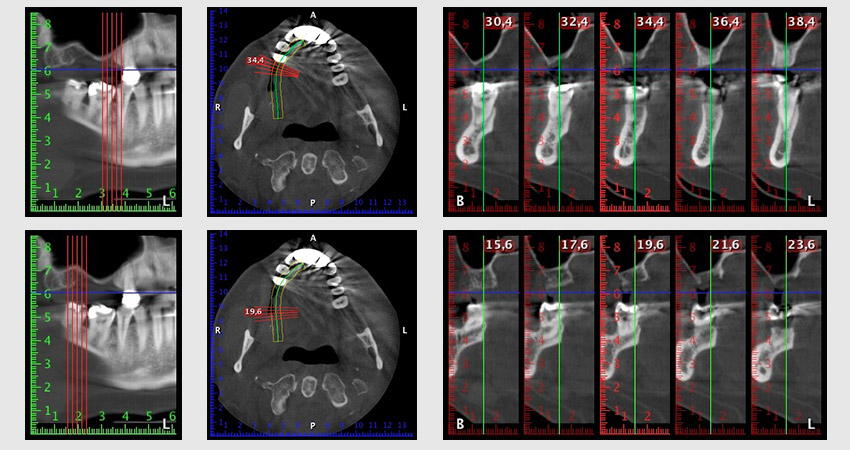

About six months after teeth 16 and 14 were extracted, a digital volume tomography (DVT, Planmeca) examination was performed for planning and risk minimization purposes. It clearly showed that the bone had not regenerated to the desired volume (Fig. 2 to 7).

Image 2 to 7: DVT with greatly reduced horizontal bone volume.

A sinus floor elevation is required in both region 16 and region 14 to guarantee a fixed restoration based on at least two implants. Relatively large-scale bone augmentation is required due to the residual bone volume being extremely low in this case. Major bone augmentation procedures are invasive and linked to higher patient morbidity, as well as being time-consuming and expensive. It is more difficult to predict the results of the treatment and the risk of failure is increased. The patient was informed of the increased risk and was offered a removable solution, which she consistently rejected.

To restrict the augmentation to region 14, and in consultation with the patient, it was planned that implant 16 would be placed, inclined, in the dorso-cranial direction (Fig. 8).